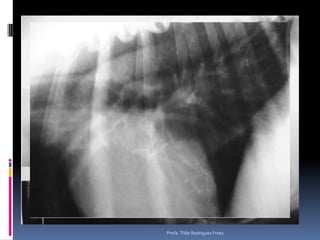

Animal: Laika, canino, fêmea, 10 anos, Pastor Alemão, FC 417/10Suspeita: Pesquisa de metástases – Nódulos em mama *Profa. Tilde Rodrigues Froes

Animal: Laika, canino,fêmea, 10 anos, Pastor Alemão, FC 417/10Suspeita: Pesquisa de metástases – Nódulos em mama *Profa. Tilde Rodrigues Froes

Exame radiográfico torácicoCuidados – padrões eventualmente detectados – diferenciação de sua relevância clínicaAspecto radiográfico pulmonarPadrão intersticial  reticular difuso Fibrose senil ObesidadeMetástases (?) – pesquisa-se linfonodos associados – buscar outra técnica diagnóstica por imagemPadrão intersticial nodular (focal o multifocal)Pequenos nódulos – vasos em cortes transversaisOutros diferenciais: degeneração costo-condral, massa externa – mamaria.Pequenos nódulos – 2-4mm – OSTEOMASUsualmente visualizados em animais de grande porte Diferenciar de MetástasesProfa. Tilde Rodrigues Froes

Exame radiográfico torácicoPesquisa de metástasesDiferentes padrõesIntersticial reticularIntersticial reticulonodularIntersticial nodularAlveolar (quando ?)Áreas cavitárias* Considerar sempre as limitações dessa análise* Em gatos* Efusão pleuralProfa. Tilde Rodrigues Froes